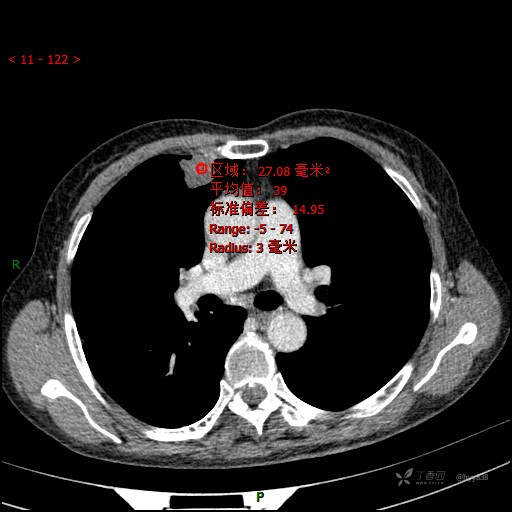

增强动脉期

CT值